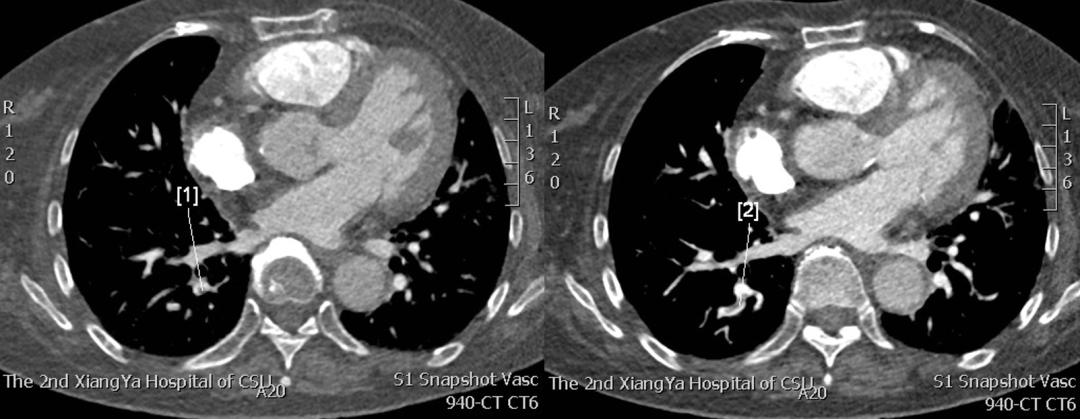

肺部CTA: 右肺下叶后基底段动脉可见充盈缺损影,提示右肺下叶后基底段动脉栓塞,余各肺动脉走行正常(见图3)。

图3:肺部CTA(2019年2月12日):右肺下叶后基底段动脉可见充盈缺损影。